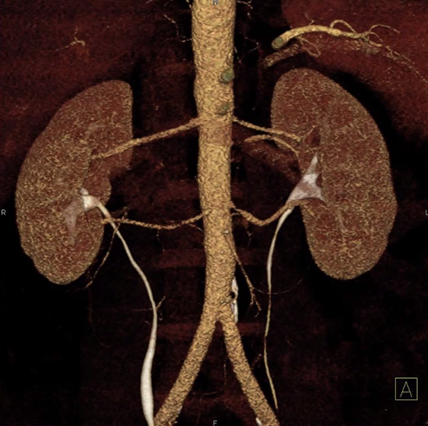

Vad ser du?

Vad kan stenos här ge upphov till?